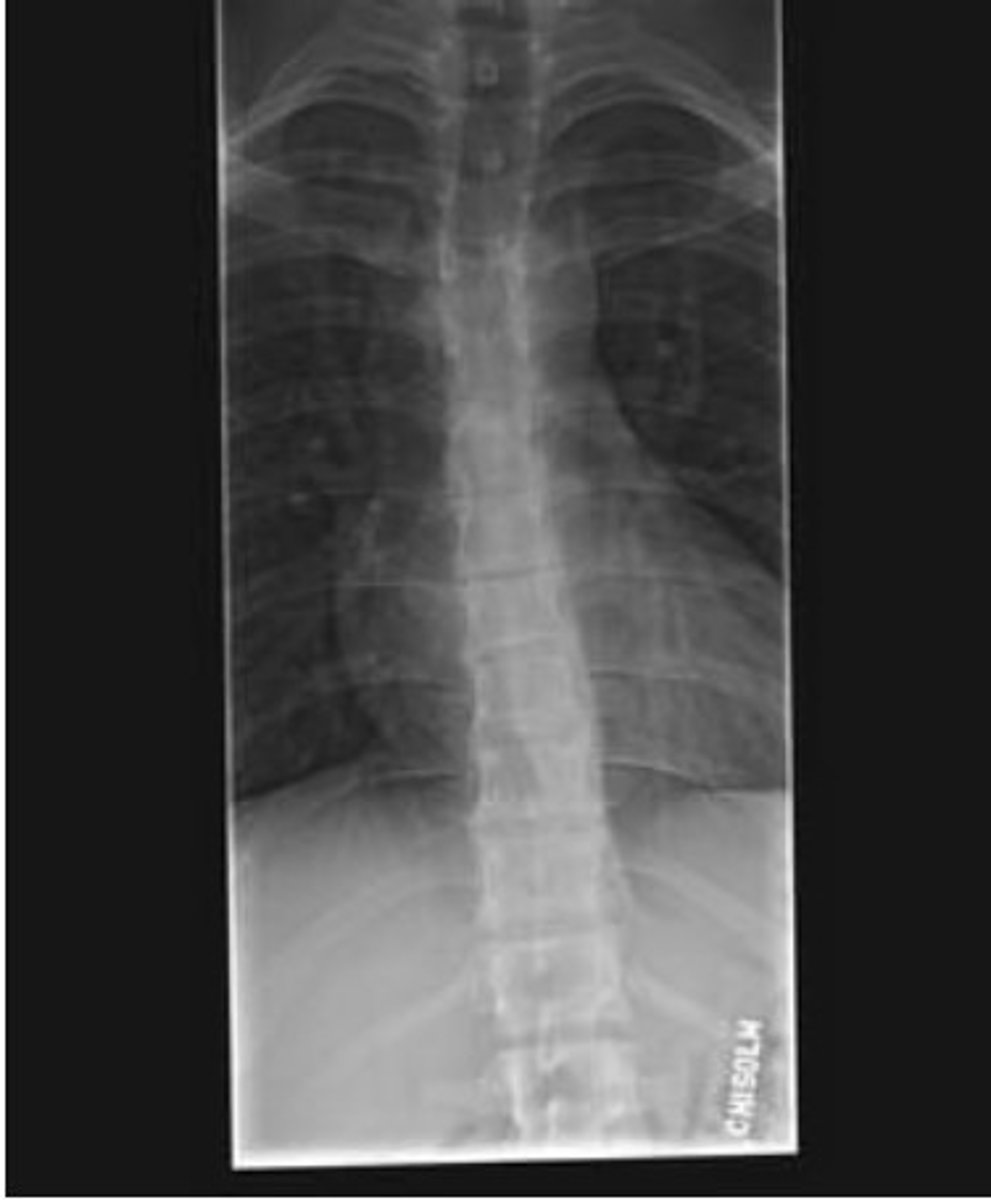

A PT is evaluating a 20-year-old male patient with a history of midback pain. Radiographic findings are shown in the picture. MRI reveals anterior wedging of the T7 9 vertebral bodies. What is the MOST appropriate diagnosis?

A. Ankylosing spondylitis

B. Osteogenesis imperfecta

C. Scheuermann's disease

D. Spondyloepiphyseal dysplasia

C. Scheunemann's disease

anterior wedging of T7 and T9 (kyphosis)

The T 1 to T8 seems very crowded

The patient age is 20 y/o - not the osteogenesis

with MRI - Schmorl Nodes